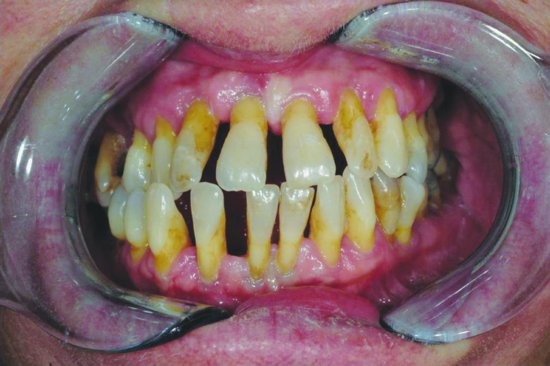

What are the different stages of periodontal disease?

Four stages of periodontal disease

Periodontal disease is broken up into four different stages, which include:

Gingivitis: This is the only stage of the disease that is reversible as it hasn’t attacked the bones yet. This is a result of plaque buildup around the teeth. Bleeding gums is one of the first symptoms you may experience. However, most symptoms of gingivitis are painless, which is what makes periodontal disease so common. Good oral hygiene and regular dental exams and routine dental cleanings can help treat and reverse gingivitis successfully.

Slight Periodontal Disease: Slight periodontal disease is the second stage of gum disease. It isn’t reversible, but can be managed. Once you reach stage two, the infection has spread to the bone and has begun to destroy bones. The bacteria have become more aggressive, which is what leads to bone less. Scaling and root planing can be used to deep clean the teeth gums. It removes deposits of bacteria that are deeply rooted in your gums.

Moderate Periodontal Disease: The third stage of periodontal disease has more probing depths, which allows for even more bacteria to attack the bones and the blood stream, too. Much like slight periodontal disease, our professional specialists will use scaling and root planing to thoroughly clean the area.

Advanced Periodontal Disease: The final stage of periodontal disease is when the infection has evolved into disease-causing bacteria. It can cause redness, swollen gums that ooze pus, sensitivity, loosening of teeth, painful chewing, severe bad breath, and bone loss. This stage requires periodontal surgery or laser therapy with the PerioLase MVP-7 TruePulse to clean the deep bacteria-filled pockets. If left untreated, stage four can lead to gaps or spacing between the teeth, the need for dentures, gum recession, and other serious health problems.

Treating periodontal disease quickly is important. At Premier Periodontics, we teach our patients good oral hygiene habits that will help them to halt the progression of their periodontal disease.